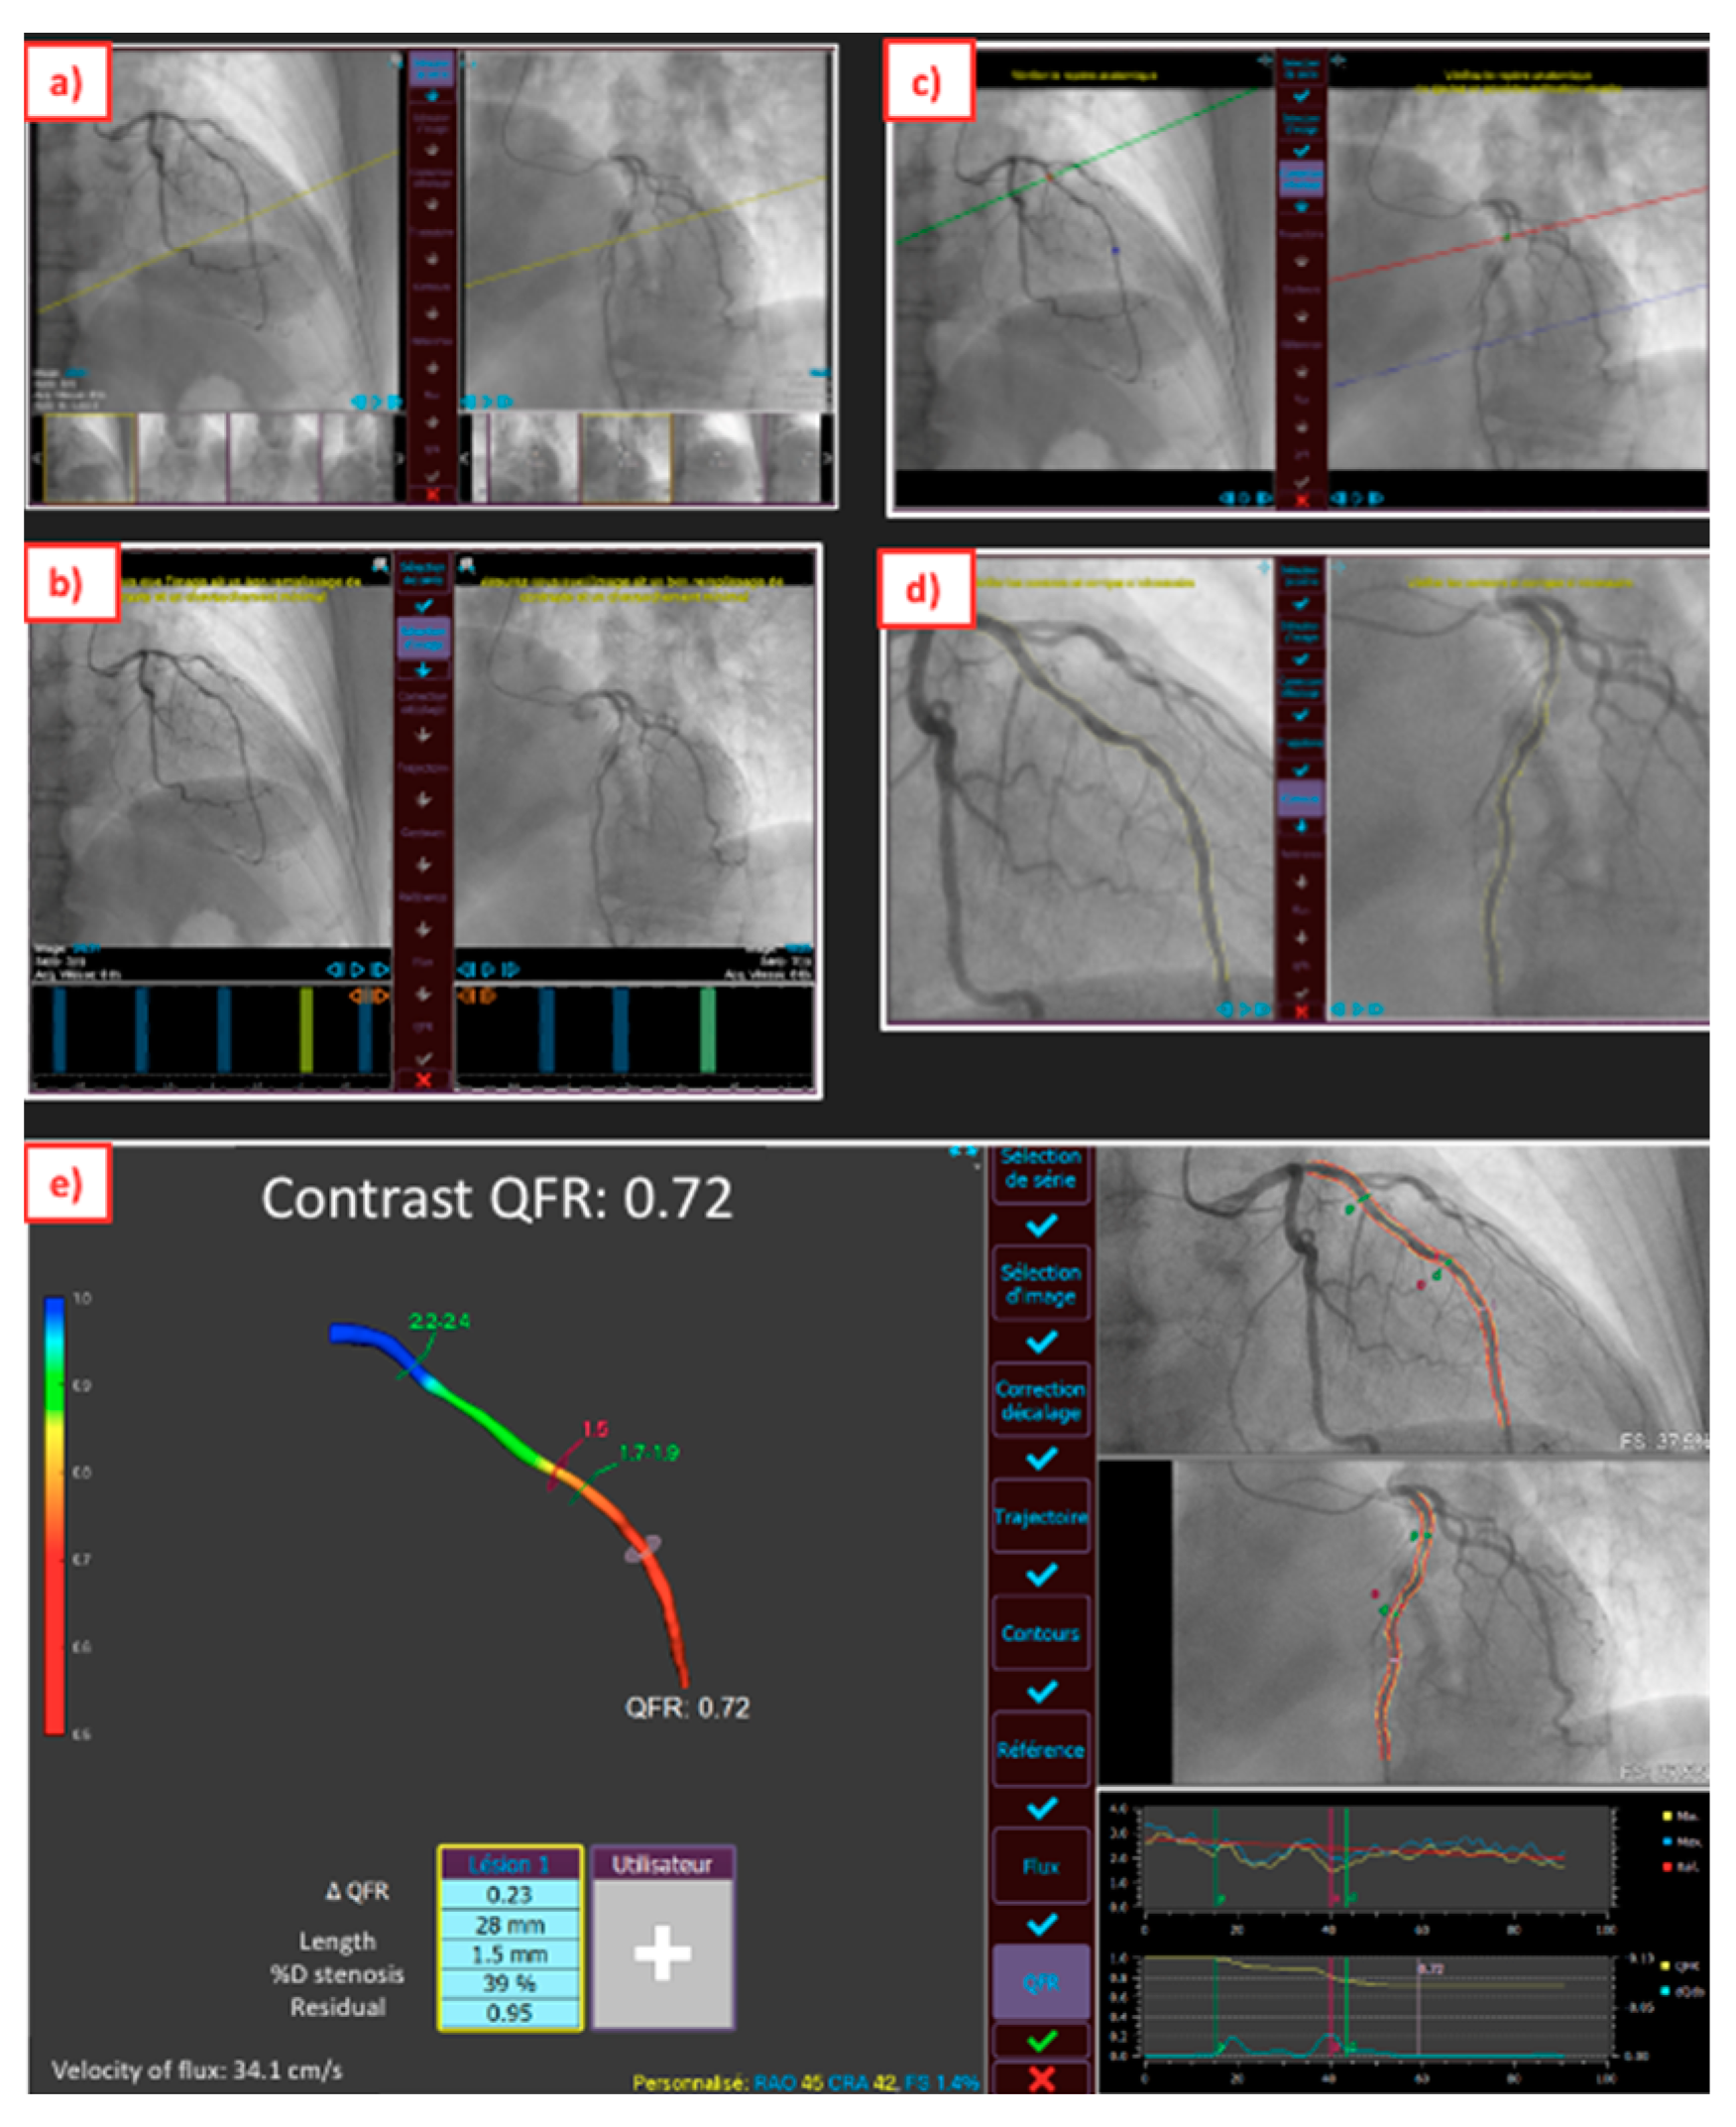

2. Upgraded ICA for Pre-PCI Time

4. Advances in ICA to Assess PCI Results

5. Virtual PCI